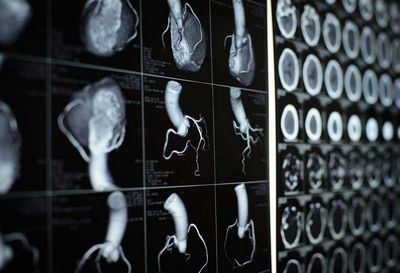

Комп'ютерна томографія (КТ) зробила революцію в галузі кардіології, забезпечивши неінвазивний і точний спосіб діагностики та моніторингу серцевих захворювань. У цій статті ми розглянемо різні способи застосування КТ у кардіології, від діагностики ішемічної хвороби серця до оцінки серцевої функції та керівництва втручаннями.

Серцево-судинні захворювання залишаються основною причиною смерті в усьому світі, щорічно забираючи понад 17 мільйонів життів. Рання діагностика та лікування серцевих захворювань має вирішальне значення для покращення результатів лікування пацієнтів. КТ стала цінним інструментом у діагностиці та лікуванні серцевих захворювань, пропонуючи візуалізацію з високою роздільною здатністю серця та навколишніх структур.

Комп'ютерна ангіографія (КТА) стала золотим стандартом для неінвазивного виявлення ішемічної хвороби серця (ІХС). Використовуючи контрастну речовину та спеціалізовані методи візуалізації, КТА може створювати детальні зображення коронарних артерій та виявляти їх закупорку або стеноз. Цей неінвазивний підхід має ряд переваг перед інвазивними процедурами, такими як коронарна ангіографія, включаючи знижений ризик ускладнень і швидший час відновлення.

КТ також може бути використана для оцінки серцевої функції, включаючи фракцію викиду (ФВ) і порушення руху стінок. ФВ є мірою того, наскільки добре серце перекачує кров і є важливим показником загальної серцевої функції. Аномалії руху стінок можуть вказувати на ділянки серця, які не функціонують належним чином, і можуть свідчити про основне серцеве захворювання.

КТ також корисна для оцінки структурних захворювань серця, включаючи клапанні захворювання серця та вроджені вади серця. КТ може надати детальні зображення клапанів і камер серця, що дозволяє поставити точний діагноз і спланувати лікування. Наприклад, за допомогою КТ можна оцінити розмір і розташування дефектів міжпередсердної перегородки (ДМПП) і дефектів міжшлуночкової перегородки (ДМШП), які можна усунути за допомогою малоінвазивних методик.